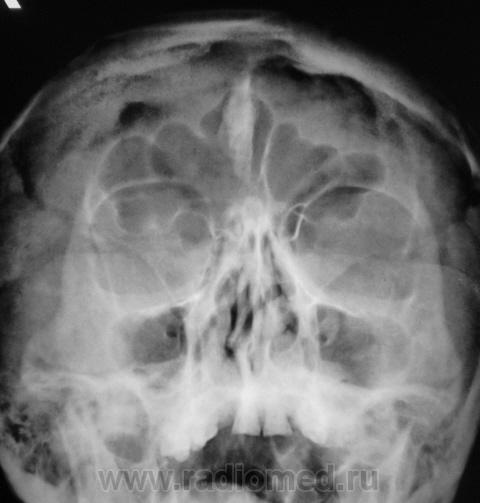

Обызвествление серповидного отростка.

А, меня, что-то смутила чешуя лобной кости...

Действительно, лобная кость какая-то "кучерявая", а в боковой проекции не доснимали?

Вены широковаты и боковые лакуны также выражены. Возможно на фоне остеопороза. Возраст, вероятно, немолодой.

Гиперпневматизация лобных пазух. Обызвествление серповидного отростка. Вероятно, повышение внутричерепного давления (сосудистый рисунок). Искривление носовой перегородки вправоsmiley. На нижнюю треть верхнечелюстных пазух "наслоились" пирамиды височных костей.